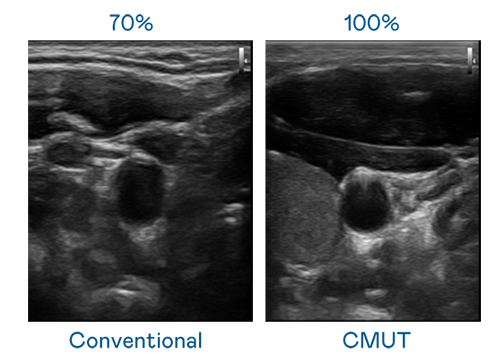

CMUT 技术是一种用电容式微机电元件来产生超音波讯号的技术。与传统 PZT 压电式技术相比,CMUT 频宽增加 30%,更宽频的超音波讯号让影像解析度大幅提升,是实现高影像品质医疗超音波扫描、促进精准医疗发展的关键技术。

超音波影像的解析度高低,首先取决于探头能发出的讯号频宽。hth华体育官网网页版 CMUT 可提供高清晰的超音波讯号,提供高频宽、高灵敏度、影像纹理细节更高的超音波影像,协助医护人员缩短影像判读时间及利用精准的医疗影像进行诊断。